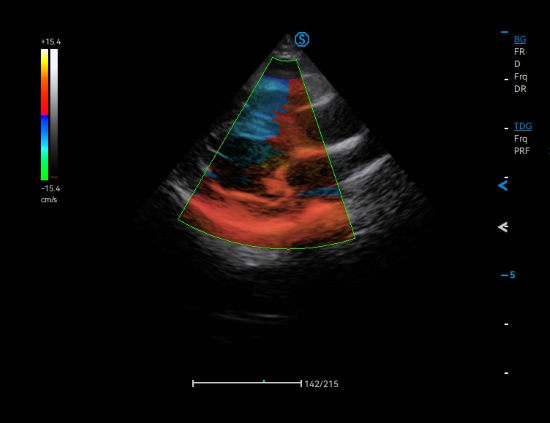

Adaptive TDI facilitates the evaluation of myocardial motion throughout the cardiac cycle, which is particularly crucial for elder dog examination.

AMM empowers assessment of cardiac wall motion with multiple sampling lines, thereby facilitating efficient diagnosis of dilated cardiomyopathy for large-sized canines

CW Mode sensitively detects high-velocity blood flow signals to identify cardiac abnormalities such as mitral regurgitation, which is commonly observed in dogs with degenerative mitral valve disease